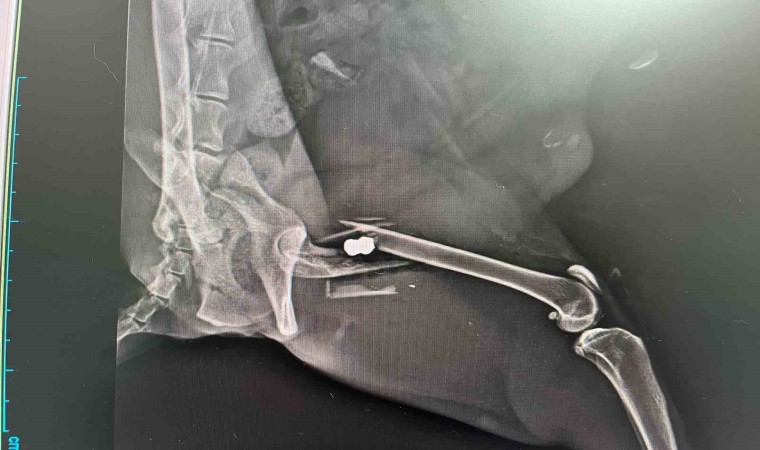

Burada ilk kontrolleri yapılan kedinin röntgeninde bacağında mermi olduğu tespit edildi. Halsiz bir durumda olan ve ayağını hiçbir şekilde kullanamayan kedi için ameliyat kararı alındı. Veteriner Hekim Hüseyin Bilgin tarafından ameliyata alınan kedinin bacak kısmındaki mermi, 3 saatlik bir operasyonla çıkarıldı. Kedinin bacağında parçalanmaya neden olan mermi çıkarıldıktan sonra parçalanan bacağa platin takıldı. Oldukça başarılı geçen ameliyat sonrasında kedinin gözlem altında kalınması kararı alındı. Her gün bakımları yapılan sokak kedisinin yaklaşık 20 gün sürecek olan tedavisinin tam tamamlanmasının ardından sahiplendirileceği belirtildi.

Kedinin durumu hakkında bilgi veren Veteriner Hekim Hüseyin Bilgin, “Olay bir duyarlı vatandaşımız tarafından bize intikal etti. Kedi aksıyor, basamıyor diye bize getirildi. Gerekli muayeneler yapıldıktan sonra röntgen görüntüsü alındı. Ve röntgende bu olayın bacak aksaması olayı değil de bir silahla, kurşunla yaralanma olayı olduğunu tespit ettik. Mermi, röntgen görüntülerinde net bir şekilde gözüküyor. Operasyonuna başladık, operasyonu da gayet iyi bir şekilde yapıldı. O atılan kurşun yerinden çıkartılıp kırılan kemik parçası ise tekrardan onarılıp platin uygulaması yaparak ameliyatı bitirdik. Kedinin şu an gayet durumu iyi” diye konuştu.